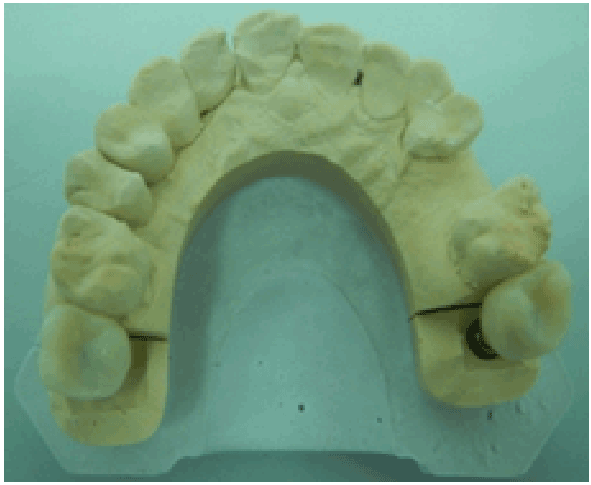

图10:实验室使用丙烯酸材料作为两种种植体的临时冠